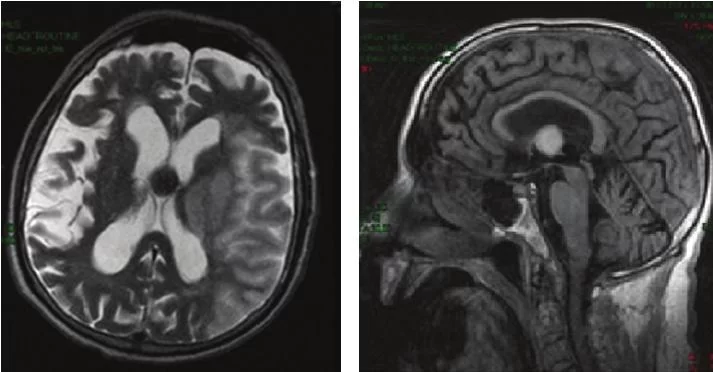

Ο απεικονιστικός έλεγχος (κυρίως με μαγνητική τομογραφία εγκεφάλου) απεικονίζει χαρακτηριστική εικόνα και συνήθως η διάγνωση μπορεί να μπεί με βεβαιότητα.

Οι ασθενείς με μικρές ασυμπτωματικές κολλοειδείς κύστεις χωρίς ενδείξεις υδροκεφαλίας μπορούν να παρακολουθούνται στενά με επαναλαμβανόμενες μαγνητικές τομογραφίες εγκεφάλου.